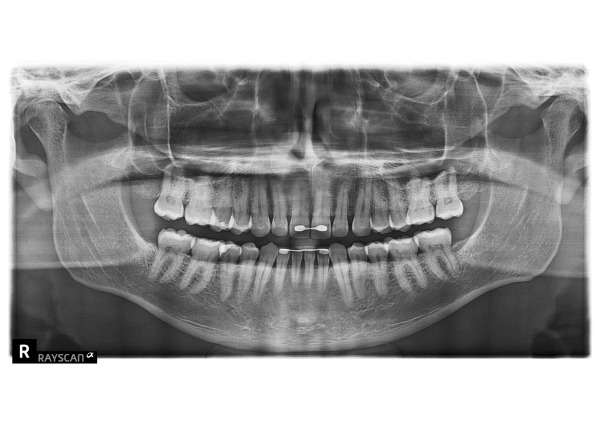

患者様は、これまで他院にて1年に一度の検診を受けられていたそうです。今回当院にて検診の継続を希望され、お口を見てみると右下の詰め物が欠けて、歯の中が虫歯になっていました。

患者様は過去に海外で矯正治療を受けたとのことで、ワイヤーで前歯を固定されていました。海外での治療歴について英語でお話を伺いながら、治療方針をご説明いたしました。

プラスチックは強度が弱く、また破損して歯を削ることはしたくないとおっしゃっていました。そのため、保険適応である銀歯とジルコニアの違い(それぞれのメリットとデメリット)をご説明し、歯にダメージのないジルコニアによる修復治療を選択されました。

1日目 虫歯を除去し、プラスチックで裏層後、型取りをしました。

2日目 ジルコニアインレーを接着性セメントで装着しました。